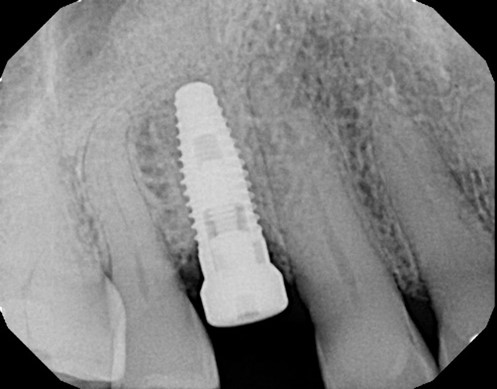

After healing and maturation of the graft to turn over into native bone, dental implant therapy can be predictably implemented and an implant body positioned for the ideal restorative position. Implant dentistry has moved away from the historical approach of placing an implant body where the bone is most favorable. The paradigm has emerged where implant treatment plans should be driven from a “restoration driven” approach. The design of implant restoration and implant body position is dictated by the ideal prosthetic position.

Due to advances in CT scanning technology, reduced costs, and improved CT scan access the osseous architecture of a proposed implant site can be pre-operatively evaluated. Treatment plans may be determined and predict whether augmentation may be indicated in an edentulous site. If it is identified that there is not enough bone or it is not in the correct position to place an implant it is better to rehabilitate the ideal alveolar ridge form first. This will permit ideal implant placement in the most appropriate prosthetic position to restore without compromise or likelihood of increased stress or restorative shortcoming in the design of the implant-prosthesis system. As dental treatment plans continue to support patients’ clinical objectives for dental implants, ridge preservation and bone grafting following tooth extraction becomes a critical component of implant site preparation. Clinical outcomes are more predictable and successful with a basic understanding of the fundamentals of bone grafting and guided bone regeneration.

Figure Legend: A 38 y.o. white male patient presented with a chief complaint of persisting pain in the upper right area, ( tooth #5) for days. Diagnosis was endodontic lesion with a hopeless prognosis (Figure 1, 2). The tooth was extracted and Regional Acceleratory Phenomena performed (Figure 3), grafted with Allograft and Resorbable membrane (Figure 4 &5) employed for Guided Bone Regeneration (GBR) and sutured (Figure 6). Four months post Extraction and Ridge Preservation surgery (Figures 7 and 8, Implant was placed (Figure 9) to be restored after osseointegration period.